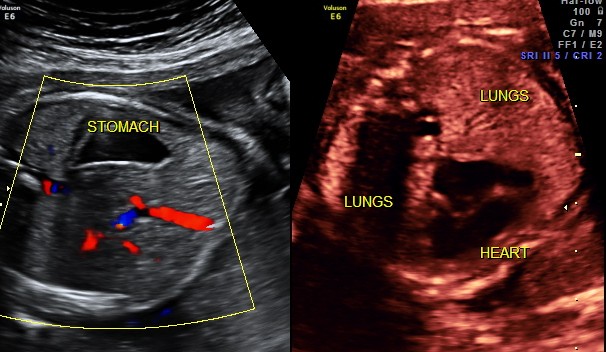

This was a 24 year old primi with history of consanguinity sent for evaluation of probable dextrocardia.

The following images were seen .